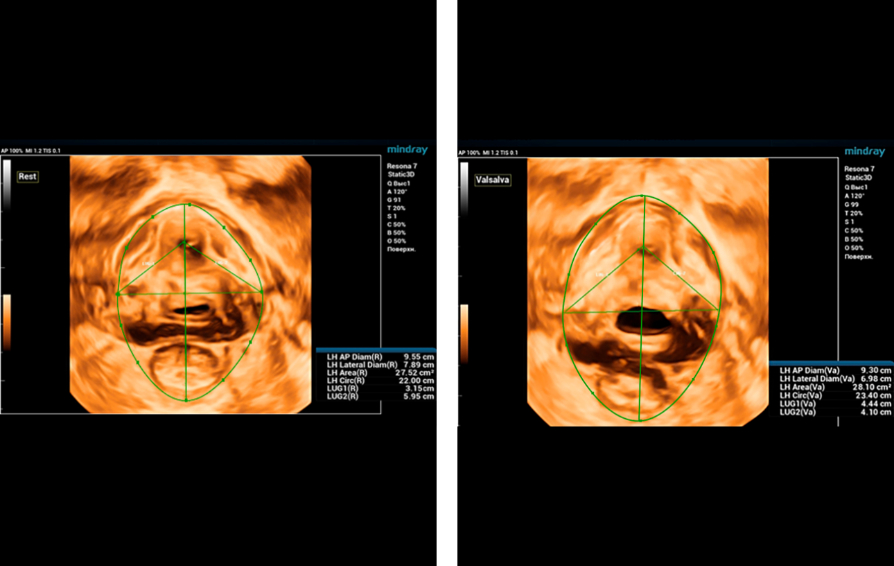

Endocavity ?? ?? ?? ???(DE10-3WU, Resona 7, Mindray)? ??? ??? ???? ?? ?? ????(Levator ani nuscle)? ??? ???. ???? ?? ??? 3~4mm? ????, ???(levator hiatus) ?? ?? - 6.13cm, LUG1(??? m ??? ??. Bulbocavernosus) ŌĆō 2.95cm ? LUG2 ŌĆō 3.15cm(?? 2.5cm ??)

??????? ??? ?? ? ??? ??? ??? ?????, ?? ??(pelvic floor) ??? ??? ?? ??(??? ?/?? ??)? ??? ???. ? ?? ???? PVA, RVA ? PUA ?? 20┬░ ???? ?????. ? ?? ???? PVA ŌĆō 134o, RVA ŌĆō 82o ? PUA ŌĆō 119o.

?? ? ???????? ?? ?? ??? ??? ???? ???? ?? ?? ??? ????. ????? ?????? ???? CUDI(??? ???? ??) ? ??? ??? ???? ? ??? ??? ? ?? ???, CUDI, ???(pessary)? ??? ?? ???(???? ??? ???? ? ? 7? ??). ?? ??? 3D ??? ? ?? ??? ??? ??? ?? ??? ?? ???? ??? ?? ?? ??? ????? ???? ?? ??? ??? ??? ????.